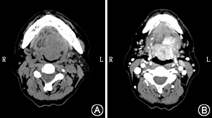

收集四川大学华西医院耳鼻咽喉头颈外科2010年1月至2018年1月收治入院,病理诊断为舌根部MEC且病历资料完整共5例患者,其中男3例,女2例;年龄27~76岁,平均53.5岁,中位年龄54岁;病程1个月至1年,平均病程约5个月;3例男性患者均有长期吸烟史,烟龄20~60年,平均烟龄36.7年,其中2例>10支/d,1例有长期饮酒史(>10年且>400 g/d)。3例以吞咽困难为主要症状,其中2例伴痰中带血,1例以声嘶和咽异物感为主诉,1例无特殊症状,为体检时发现颈部包块就诊。查体均可见舌根部来源肿物,其中2例单纯位于舌根;1例累及咽侧、咽后壁,会厌及喉;余2例累及扁桃体下极、咽侧壁和会厌谷,其中1例还侵及喉和梨状窝。舌根部肿物大小为1.5~6.0 cm(图1),质硬,其中4例肿物表面黏膜较光滑,1例表面粗糙糜烂,呈菜花状新生物,与周围组织有粘连。5例行CT及MRI检查,均显示舌根部有大小不等的软组织团块影,边界不清,增强后不均匀强化,其中3例伴有颈部淋巴结不同程度增大(图2)。

通常间接喉镜或电子纤维喉镜即可较容易地发现舌根部的该实性占位病变,进一步的诊断包括明确肿物性质、浸润深度、累及范围及有无淋巴结转移。影像学检查是必要的,舌根部MEC多表现为大小不等的软组织团块影,边界不清,增强后多呈不均匀强化。颈部增强CT有助于判断颈部淋巴结转移,MRI则能够更精确地显示肿瘤的范围、边界、与周围结构的关系及浸润深度[4,5]。本组患者术前均行CT/MRI检查,结果提示舌根部有大小不等、边界不清的软组织团块影,3例有颈部淋巴结肿大,其中2例术后病理检查证实有淋巴结转移。